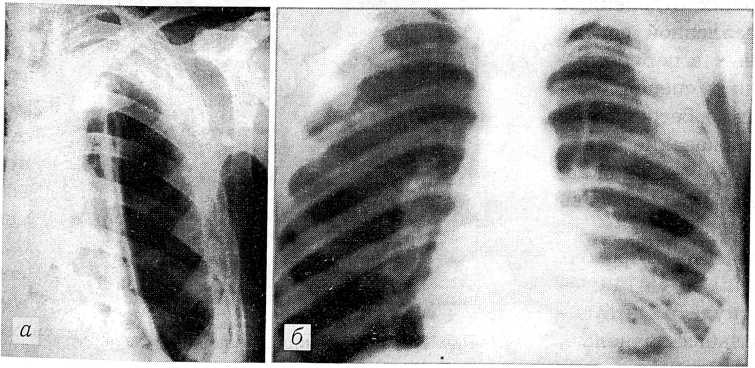

Рис. 5. Рентгенограммы раненого с проникающим ранением левой половины грудной клетки. а — гемопневмоторакс, смещение средостения; б — после постоянного вакуумирования на электроаппарате Каплана: расправление легкого, нормальное положение средостения.

В торакальное отделение (200 коек) госпитализировали раненых с разного вида тяжелыми проникающими ранениями грудной клетки, которые осложнялись закрытым и открытым гемо- и пневмопиотораксом, ранением легких, бронхов, смещением средостения (рис. 5). Встречались единичные случаи открытых и закрытых ранений перикарда и сердца (рис. 6). Общая летальность была немалой.